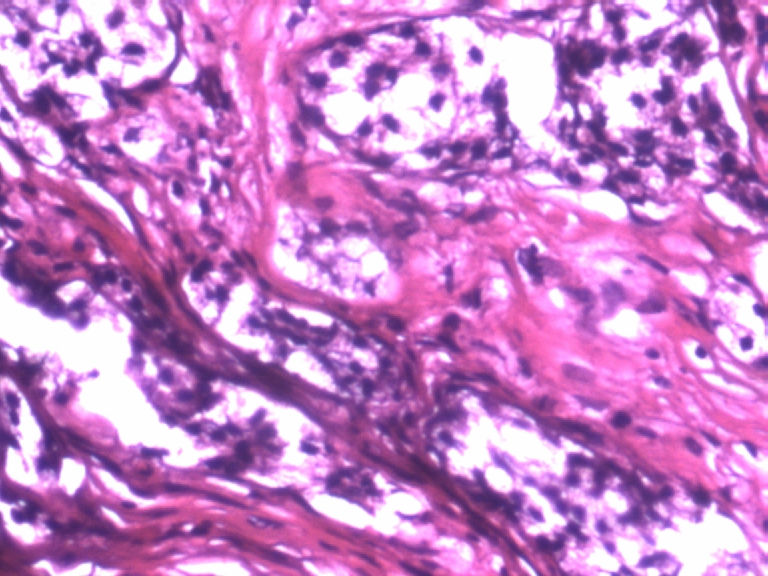

男,50岁,阑尾长7厘米,直径0.4---0.6厘米。剖开:尖端看见淡黄色区,不规则,界限欠清,0.15*0.2厘米,质中。

×参考诊断

考虑阑尾类癌

像类癌,有些粘液,标记一下Syn、CgA,有可能是杯状细胞类癌

像粘液腺癌

按照胃肠胰腺神经内分泌肿瘤WHO2010分类,该例应属于NET G1(神经内分泌瘤,1级)。需标记Syn, CgA, Ki67.

倾向神经内分泌肿瘤,建议做CgA、SYN、Ki-67检查。

阑尾的神经内分泌肿瘤我们已经碰到好几例了,一般都在阑尾尖端,取材一定要规范,这样可以减少漏诊率。